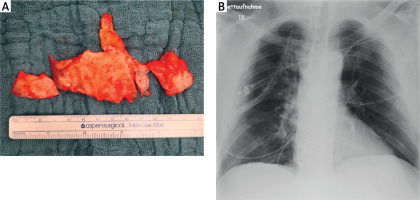

Figure 2

A – A section of the parietal pleura with representative calcified plaques, resected for histological examination. B – Postoperative chest X-ray showing no evidence of pneumothorax or hemothorax